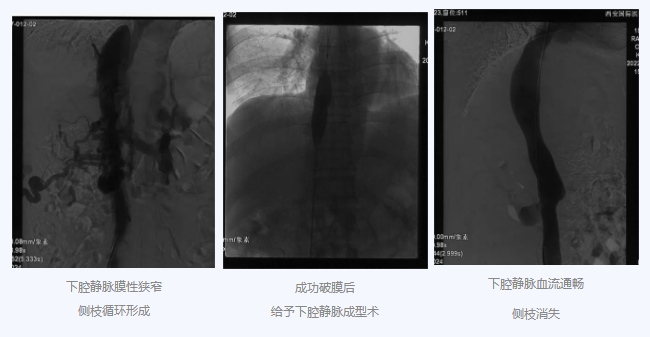

入院后,在韓國宏院長的安排下,臨床經(jīng)驗豐富的醫(yī)師給老謝做了B超、CT 等檢查,結果顯示:三支肝靜脈近心端閉塞,肝內(nèi)側(cè)枝循環(huán)形成,下腔靜脈近心房入口處隔膜樣狹窄,隨后的DSA血管造影也證實:下腔靜脈狹窄,且有側(cè)枝形成,最終確診困擾老謝20年的疾病為混合型布加綜合征,是一種罕見病。

明確診斷后,韓院長帶領團隊縝密分析老謝的病情,為其制定最佳的治療方案,考慮到老謝的根本病因是下腔靜脈阻塞,介入手術成為首選治療方法,通過微創(chuàng)介入手術,可準確打通患者的閉塞血管,癥狀迅速緩解。做好充分術前準備后,為患者行“下腔靜脈成型術”,精準定位快速貫通,閉塞的下腔靜脈順利開通,手術圓滿完成。